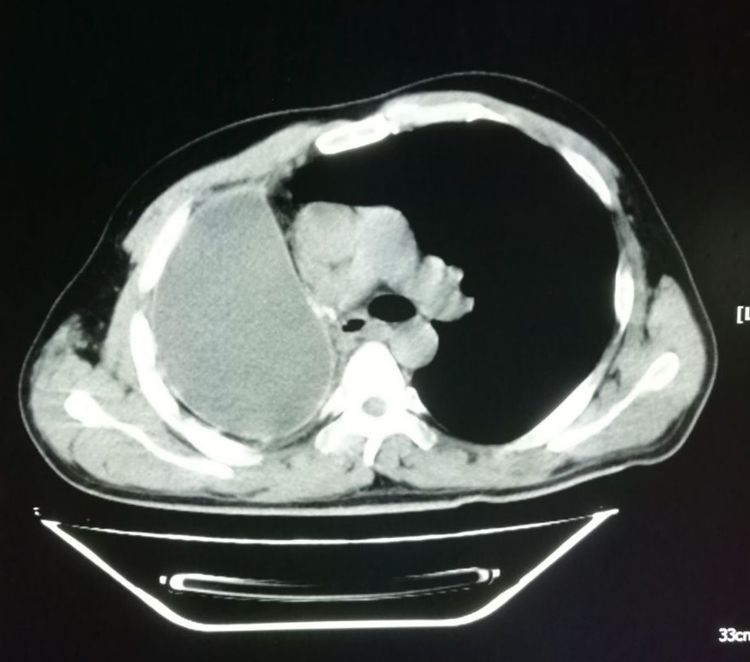

下图是一位有点消瘦的老爷子,吸烟接近50年,咳嗽、痰中带血,胸部CT加支气管镜发现左侧肺鳞癌,肿瘤内部已经形成了空洞:

在前面的“豪大夫讲肺结节”系列中,我们提到过伴有空洞形成的肺鳞癌预后差,中位生存期平均只有17个月,而没有空洞者,可以达到92个月,差异巨大。

这是因为空洞型肺癌生长更迅速,病理上更容易发生坏死;更容易侵犯血管、淋巴管和胸膜。

在周围型肺癌中,肺鳞癌的空洞发生率大约是17%,腺癌是7%。

这位老爷子的家属全面考虑后选择冒险赌一把,做了左侧全肺切除。

手术很成功!

术后第3年复查的时候:

我们可以看到左侧胸腔形成了术后残腔。